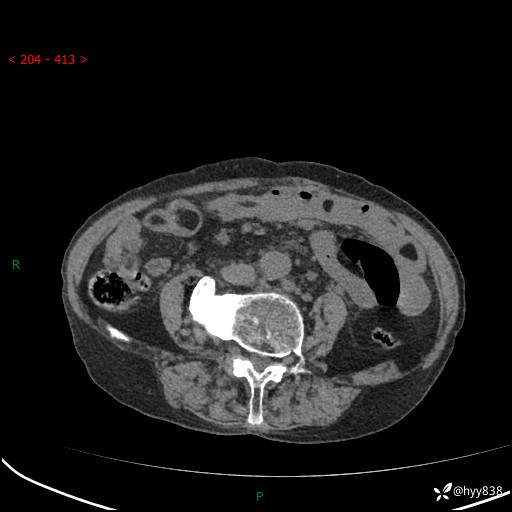

全腹部CT平扫